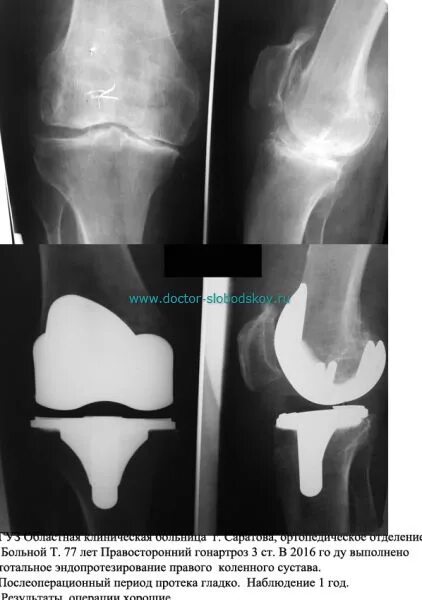

Гонартроз мрт